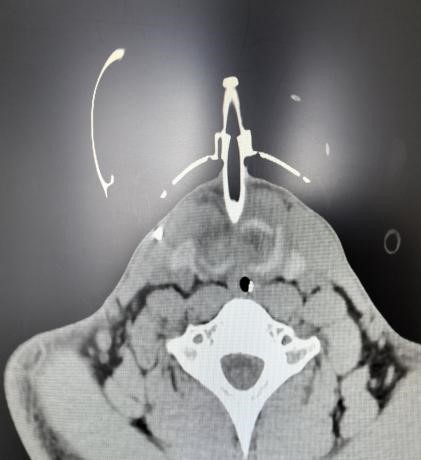

患者入院时虽神志尚清,但已出现声音嘶哑、颈部疼痛、胸闷气喘等危险信号,血氧饱和度持续下降。我院急诊团队评估后立即启动最高级别预警,迅速完成生命体征监护和检查的同时,敏锐地察觉到患者颈部正在快速肿胀,这是皮下气肿的典型表现,预示着气道可能存在严重破损。我院耳鼻喉科专家通过喉镜探查,做出了关键性判断:高度怀疑喉软骨骨折、气管断裂。后续CT检查结果印证了这一判断,患者双侧颌面部、颈部、胸部乃至纵隔内出现了大量积气。更危急的是,断裂处漏出的气体已形成双侧张力性气胸,双肺被压缩均近50%,心脏和大血管严重受压,情况十分危急!